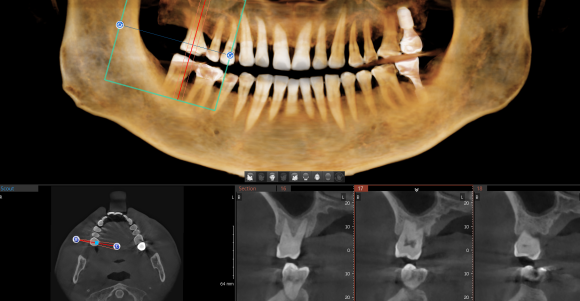

증상과 상태에 따라 큐레이, 치근단 X-ray, CT 등을 적절히 활용하여 문제의 원인을 다양한 방법으로 확인하는걸 원칙으로 있습니다.

CT 촬영 사진